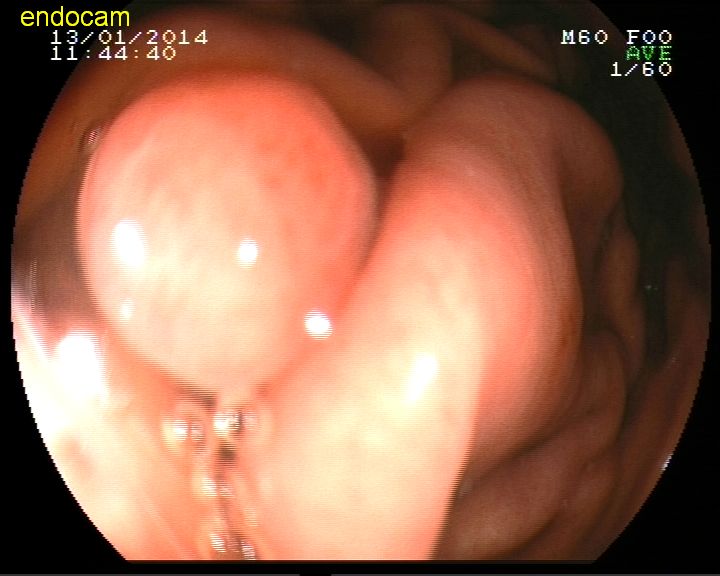

Kolonda polip